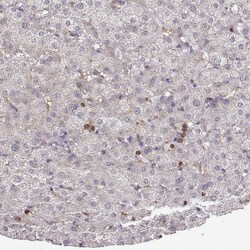

Invitrogen™ PILRA Polyclonal Antibody

Supplier: Invitrogen™ PA566000

| Immunohistochemistry (Paraffin) | |